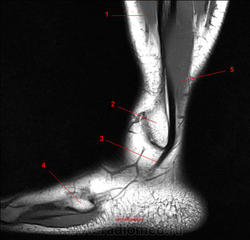

Рис. 17

1, Длинный разгибатель пальцев. 2, Малоберцовая кость. 3, Сухожилие длинной малоберцовой мышцы. 4, Пятая плюсневая кость. 5, Короткая малоберцовая мышца.